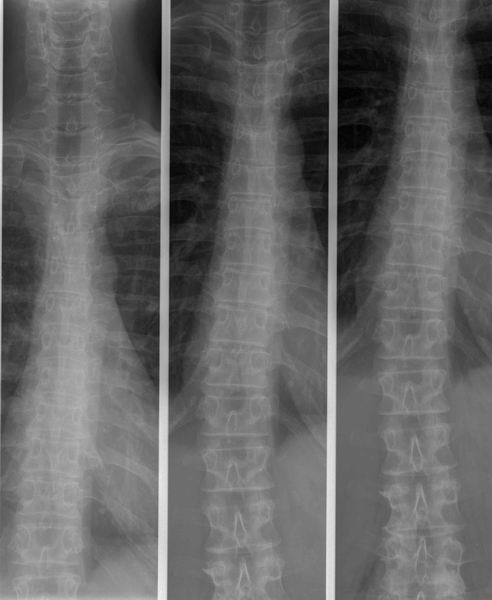

Dorsale wervelzuil